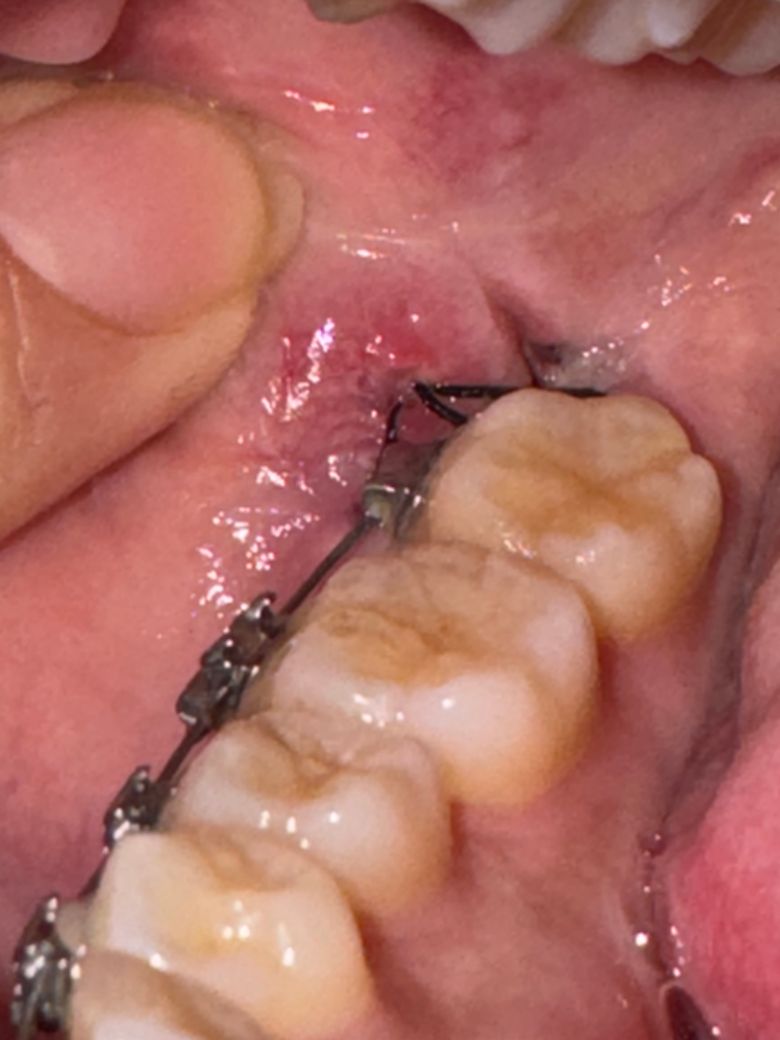

교정기가 살을 파고든거같아요 ㅠㅠ 너무 아파오ㅠㅠㅠㅠㅠㅠ

하악매복수평 사랑니 뽑은지 5-6일정도 됐는데 교정기랑 실빱이랑 엉킨건지 교정기 철사가 튀어나와서 찌르는건지

입 벽쪽이 너무 아파요 ㅠ 병원가면 해결해주나요? 해결해주면 가고 안해주면 그냥 실밥푸는날 갈려고요ㅠㅠ

해당 부위에 압박이 가해지며 상처가 생긴 것 같습니다. 특별히 치료를 할 수는 없어 실밥푸는날 가보시면 됩니다.

사랑니 발치를 한곳에 봉합을 해놓으면서 잇몸이 당겨지게된거 같습니다. 당겨지면서 교정장치에 자극을 받은거 같으며 실밥을 제거하면 괜찮아 질꺼에요.

네 교정장치가 연조직을 자극해 염증, 궤양이 생긴 것으로 보입니다. 교정치과가서 한번 체크해보시기 바랍니다.

교정기 철사가 빌치부위를 자극하여 염증으로 붉고 자극받은 것으로 보입니다. 치과에 방문하여 치아왁스를 받아서 해당부위철사에 부착하는 것이 도움이 될수 있습니다.

해당부위에 염증이 덧나지 않도록 헥사메딘 가글액으로 가글하여 관리하여 주길 권합니다.